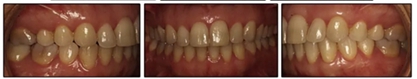

患者決定采用非手術(shù)治療方法,側(cè)貌沒有任何預(yù)期的變化。治療后面部照片(圖5)顯示她改善的微笑和側(cè)貌,包括尖牙保護合。由于先天性第一前磨牙缺失,右磨牙關(guān)系為III類。治療后牙齒石膏模型(圖6)顯示實體牙齒交錯排列情況,并且全景X線片顯示可接受的牙根平行度而且沒有牙根吸收表現(xiàn)(圖7)。最終的頭影測量片(圖7)證實了面部評估,并且描跡圖顯示深覆蓋的改善,同時保持上頜切牙位置并通過測量ANB角度和Wits評估改善骨性II級關(guān)系(表)。治療前后的疊加圖顯示由于下頜切牙前傾的增加改善了下唇平衡(圖8)。如相關(guān)治療計劃所預(yù)測的那樣,B點出現(xiàn)。A進行牙科錐形束計算機斷層掃描以記錄下頜前牙區(qū)的骨質(zhì)變化。如預(yù)期的那樣,由于治療導(dǎo)致該區(qū)域的骨量增加(圖9)。

最終評估結(jié)果如下:(1)美觀改善; (2)達到了生理功能; (3)患者對治療結(jié)果完全滿意; (4)上頜尖牙的角度和下頜切牙的傾斜度有所改善(表); (5)形成了穩(wěn)定的牙周終點,并觀察到附著齦的厚度改善; (6)病人會從下頜前移中受益,但她不想改變她的側(cè)貌; (7)長期變化(6年)是穩(wěn)定的,在B點再生的骨保持穩(wěn)定,咬合關(guān)系得到改善(圖10和11;表)。